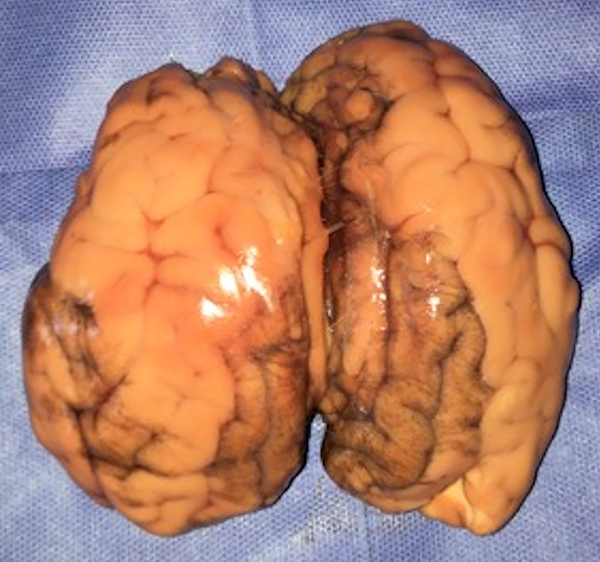

Figura 1: Cerebro bovino completo. La imagen muestra la conformación de un cerebro bovino completo, podemos apreciar la similitud con el cerebro humano en cuanto a su superficie externa.

El modelo consiste en la utilización de un cerebro bovino (de preferencia utilizar la pieza completa) (fig. 1) y de pequeñas unidades de membrana amniótica, que se colocan envolviendo las tapas de botellas de plástico, para permitir la fenestración y dilatación de la misma (fig. 2 a-b). Éstas se disponen dentro de un recipiente esférico de poliestireno expandido (fig. 3 a-b), el cual se fenestra en la parte superior para permitir el ingreso del endoscopio. Para poder utilizar el monopolar debe colocarse dentro del recipiente el terminal del cable, que proviene de la consola, directamente en contacto con el tejido cerebral (fig. 4). Finalmente cerramos la esfera de poliestireno expandido y la llenamos por completo con solución fisiológica o agua corriente (fig. 5).

Figura 1: Cerebro bovino completo. La imagen muestra la conformación de un cerebro bovino completo, podemos apreciar la similitud con el cerebro humano en cuanto a su superficie externa.